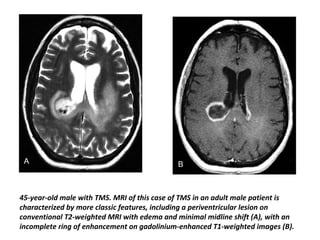

45-year-old male with TMS. MRI of this case of TMS in an adult male patient is

characterized by more classic features, including a periventricular lesion on

conventional T2-weighted MRI with edema and minimal midline shift (A), with an

incomplete ring of enhancement on gadolinium-enhanced T1-weighted images (B).